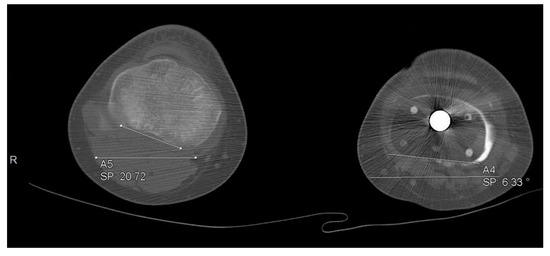

3.5. Rotational and Angular Deformities

Figure 5.

Rotational deformity of 26 degrees in one of our patients.